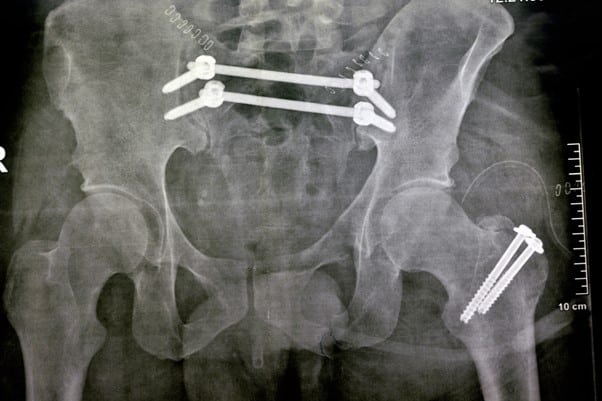

Abstract | Nov 19, 2024

Mortality Outcomes in Treating Intertrochanteric Hip Fractures Using Intramedullary Nails and Dynamic Hip Screw: A Retrospective Study

Rehman Sohail, et al.

Objective: We aimed to investigate the increased mortality associated with intramedullary nails (IMN) as compared to dynamic hip screws (DHS) in treating trochanteric hip fractures...Read More